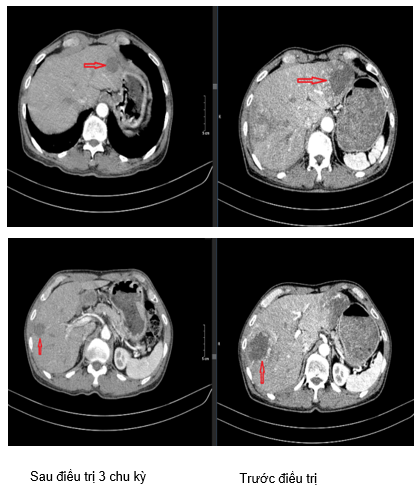

Hình 1. Hình ảnh tổn thương phổi phải phát triển lan vào trung thất: Sau 3 chu kỳ điều trị kích thước giảm xuống còn khoảng 16x29mm (hình bên trái) so với trước điều trị kích thước khoảng 62x65mm (hình bên phải).